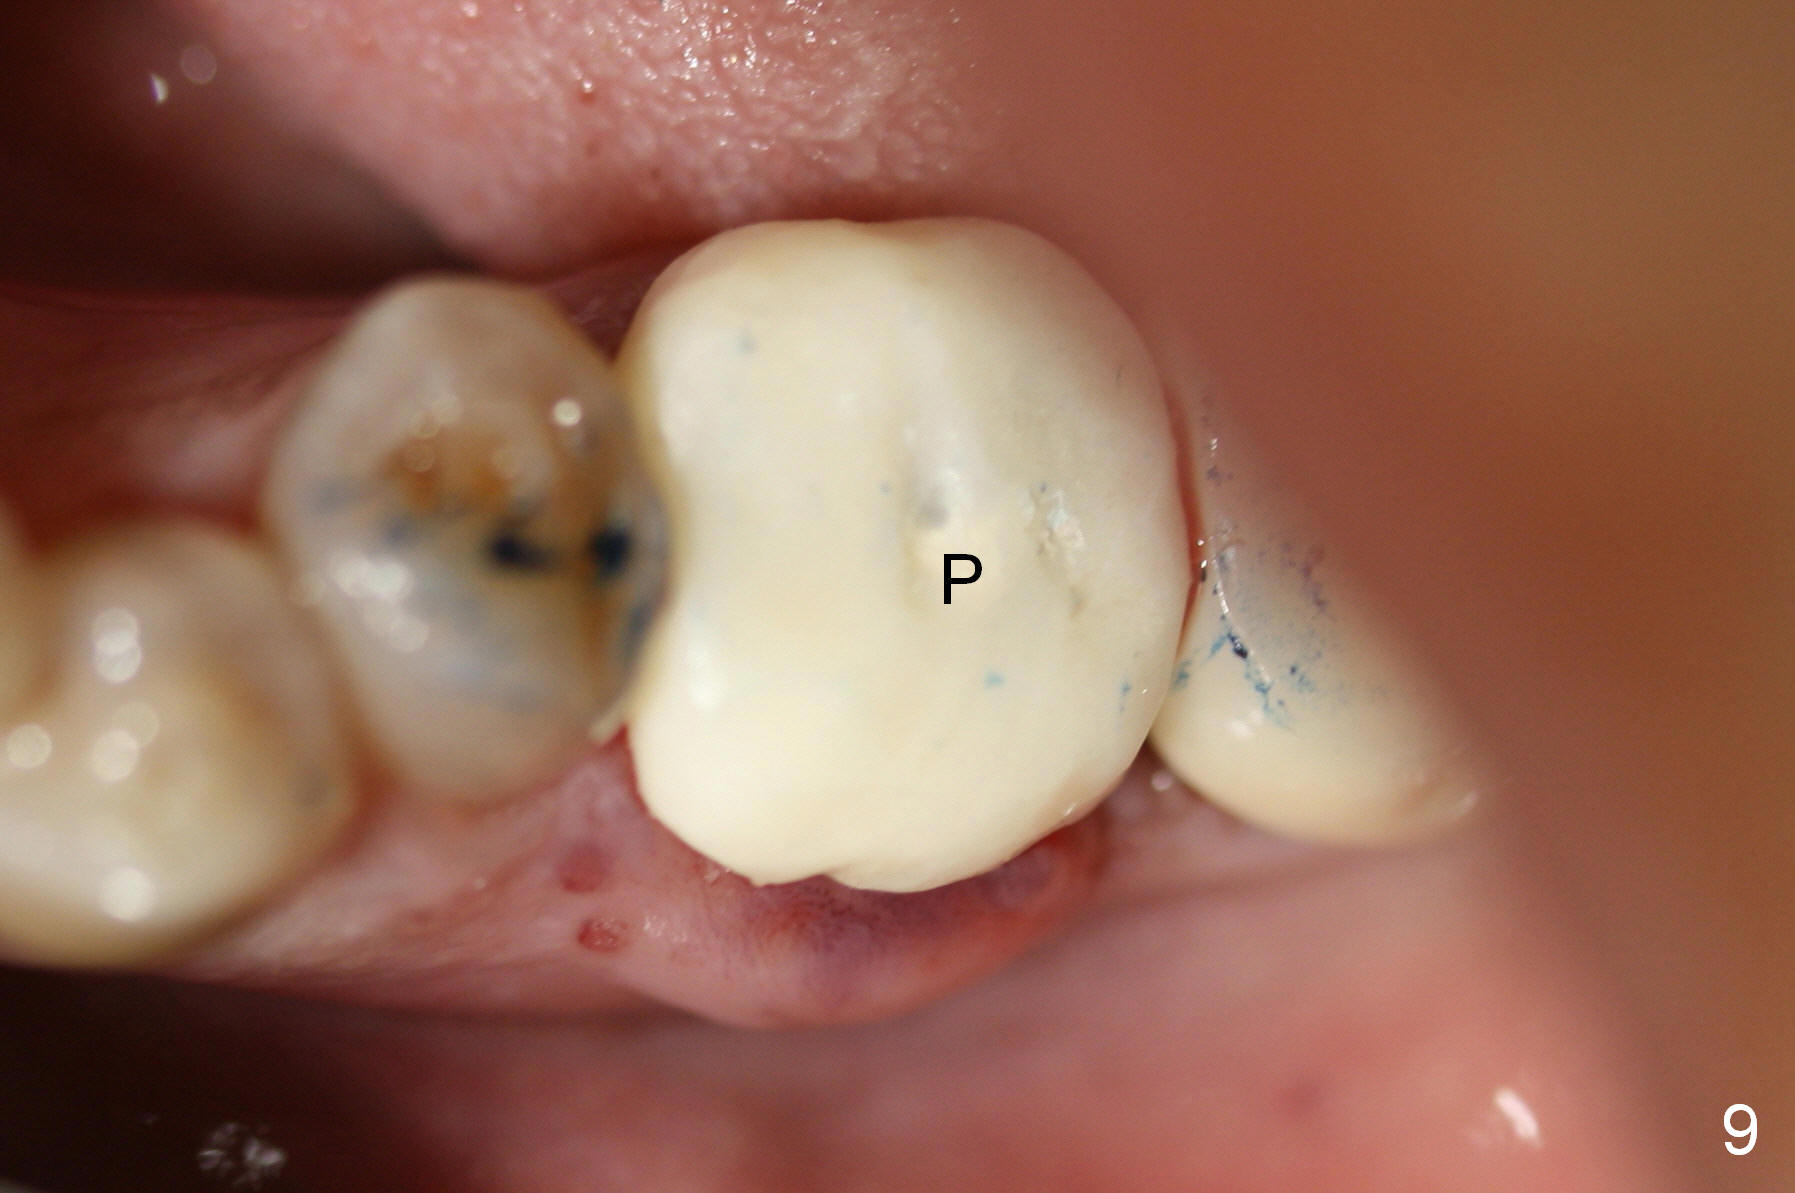

A 47-year-old lady lives out of town and presents to clinic with chief complaint "lower left back tooth easily bleeding with food impaction". Dental history and examination reveals failure of endo retreat of the tooth #19 (Fig.1), buccal gingival swelling (S), open access (A) and furcal and mesial periapical radiolucency (Fig.2 *). She is pleased to know availability of immediate implant and immediate provisional and accepts and receives the treatment at the same visit. The immediate implant (tissue-level) is designed to be as large as 7 mm and as long as 17 mm (Fig.3). To reduce paresthesia (yellow dashed line: the possible upper border of the Inferior Alveolar Canal)), a shorter implant (14 mm long in red line) is preferred. The tooth is extracted with sectioning. Granulation tissue is removed from the furca. The buccal plate appears to be intact. The septum is flat (Fig.4,10a S). Osteotomy starts in the middle of the septum with a 1.2 mm drill (Fig.10b red circle). As osteotomy increases in diameter (Fig.5 O), the apical end appears to be deviated mesiobuccally (Fig.10c large red circle). When a 6x17 mm tapered tap is being placed 14 mm deep (Fig.6 T), vibration of the buccal plate is seemingly felt at the apex (Fig.10d green circle). Further osteotomy may perforate the buccal plate. A 6x14 mm tissue-level implant is placed with >60 Ncm of insertion torque (Fig.7,8 I), followed by a 5x3 mm abutment (A) and bone graft (* in the remaining socket gap). An immediate provisional is cemented without occlusal contact (Fig.9 P).

Buccal gingival swelling and mesial periapical radiolucency suggests weakened buccal plate. Osteotomy in the septum should be initiated more lingually (Fig.10e). When the osteotomy starts being deviated, correct as early as possible with a Lindamann bur and preferably over-correct (Fig.10f blue circle). The final implant placement may not encroach the buccal plate (Fig.10f red circle). Three weeks postop, the buccal infection dissolves (Fig.11). What has not disappeared is the buccal undercut (*): the basis for potential buccal perforation. Buccolingual osteotomy trajectory should be adjusted intraoperatively accordingly.